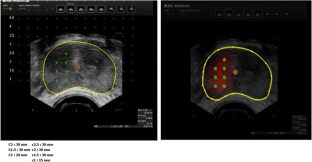

Vascular targeted photodynamic therapy (VTP) with WST11 is a novel non-thermal focal treatment for localized prostate cancer that has shown favorable and early efficacy results in previously published studies. In this work, we investigate the efficiency of automatic dosimetric treatment planning. An action model established in a previous study was used in an image-guided optimization scheme to define the personalized optimal light dose for each patient. The calculated light dose is expressed as the number of optical cylindrical fibers to be used, their positions according to an external insertion grid, and the lengths of their diffuser parts. Evaluation of the method was carried out on data collected from 17 patients enrolled in two multi-centric clinical trials. The protocol consisted of comparing the method-simulated necrosis to the result observed on day 7 MR enhanced images. The method performances showed that the final result can be estimated with an accuracy of 10%, corresponding to a margin of 3 mm. In addition, this process was compatible with clinical conditions in terms of calculation times. The overall process took less than 10 min. Different aspects of the VTP procedure were already defined and optimized. Personalized treatment planning definition remained as an issue needing further investigation. The method proposed herein completes the standardization of VTP and opens new pathways for the clinical development of the technique.